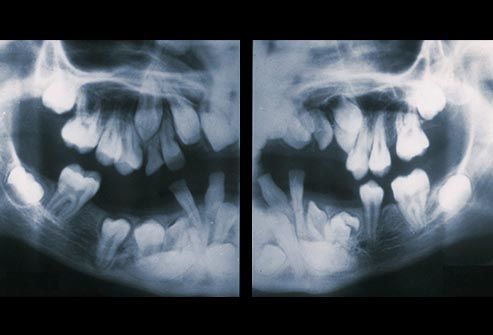

Problemet me dhëmbët e pjekurisë.

Nëse dentisti juaj thotë se dhëmbët tuaj të pjekurisë, ose molarët e tretë po dalin pa probleme, konsideroni veten me fat. Shumica e njerëzve – diku 90% – kanë të paktën një dhëmb të pjekurisë që është i ndikuar apo jo në gjendje të rritet plotësisht. Problemet me dhëmbët e pjekurisë mund të shkaktojnë prishjen e dhëmbëve, dëmtimin e dhëmbëve fqinjë si dhe sëmundje të mishit të dhëmbëve. Dhëmbët e pjekurisë përgjithësisht dalin në mes të moshës 17 dhe 25. Dentisti juaj duhet te ndjekë progresin e tyre. Nëse ju shkaktojnë ndonjë problem, ju sigurisht do të keni nevojë t’i largoni.